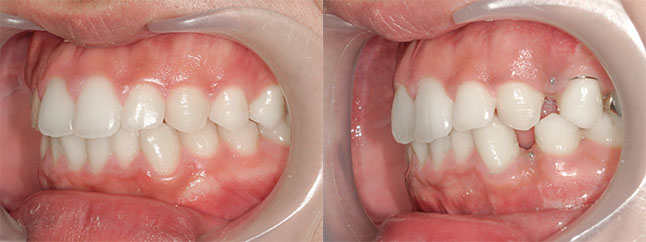

奈良県 20歳 女性

執刀医 辻和志

【治療内容】上下のアゴが前に出ていたため、上下のアゴの骨を切って後ろにさげました。

【費用】上下セットバック 2,307,800円(税込)

【リスク】全身麻酔で行うため全身の健康状態が悪い方は行うことができません。また、手術当日は安静にしていただく必要があります。